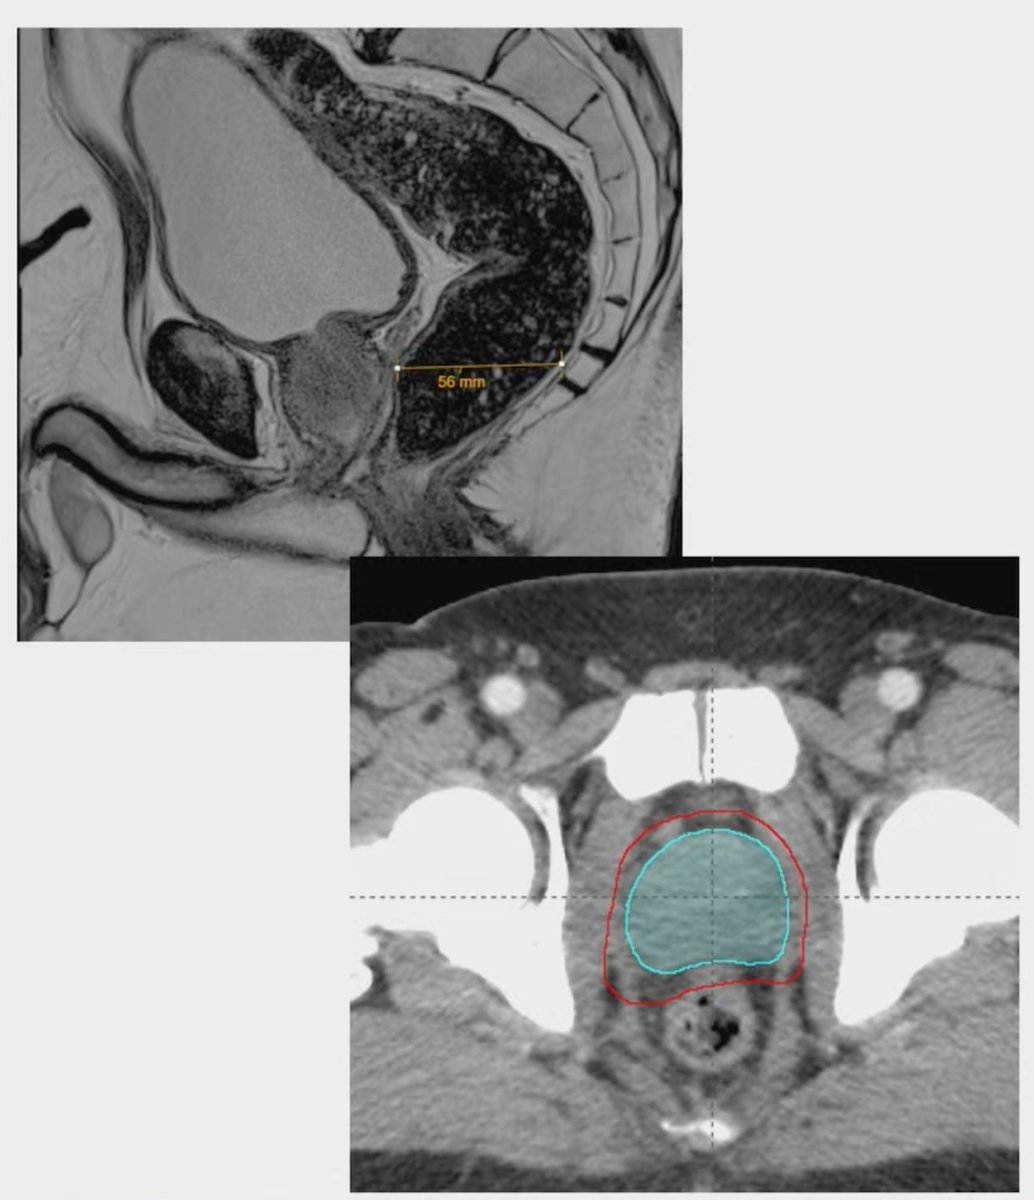

#ASTRO25 Dr. Neil Desai presents hydrogel spacer QA in the multi-center POTEN-C RCT of NV-sparing SAbR for localized PCa: 📊 86% post-spacer MRI 🧪 68% had optimal SQS=1 🧱 74% had no rectal wall infiltration 💥 SQS ↑ = ↓ rectal Dmax (p<0.01) 📉 No short-term GI tox or QoL